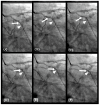

Background: In the study of coronary artery disease, the mechanisms underlying atherosclerosis initiation and progression or regression remain incompletely understood. Our research conceptualized the cardiovascular system as an integrated network of pumps and pipes, advocating for a paradigm shift from static imaging of coronary stenosis to dynamic assessments of coronary flow. Further review of fluid mechanics highlighted the water hammer phenomenon as a compelling analog for processes in coronary arteries. Methods: In this review, the analytical methodology employed a comprehensive, multifaceted approach that incorporated a review of fluid mechanics principles, in vitro acoustic experimentation, frame-by-frame visual angiographic assessments of in vivo coronary flow, and an artificial intelligence (AI) protocol designed to analyze the water hammer phenomenon within an acoustic framework. In the analysis of coronary flow, the angiograms were selected from patients with unstable angina if they had previously undergone one or more coronary angiograms, allowing for a longitudinal comparison of dynamic flow and phenomena. Results: The acoustic investigations pinpointed pockets of contrast concentrations, which might correspond to compression and rarefaction zones. Compression antinodes were correlated to severe stenosis, due to rapid shifts from low-pressure diastolic flow to high-pressure systolic surges, resulting in intimal injury. Rarefaction antinodes were correlated with milder lesions, due to de-escalating transitions from high systolic pressure to lower diastolic pressure. The areas of nodes remained without lesions. Based on the locations of antinodes and nodes, a coronary acoustic action map was constructed, enabling the identification of existing lesions, forecasting the progression of current lesions, and predicting the development of future lesions. Conclusions: The results suggested that intimal injury was likely induced by acoustic retrograde pressure waves from the water hammer phenomenon and developed new lesions at specifically exact locations.